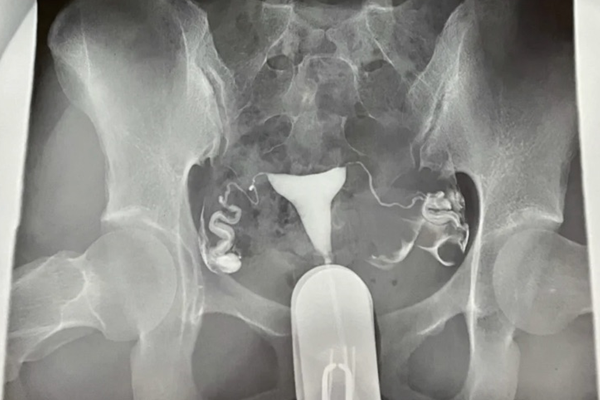

造影是不能把輸卵管通開的。子宮的輸卵管造影,只是一個檢查,而不是一個治療手段。子宮輸卵管造影是將碘劑直接由子宮頸管注入子宮腔,在經子宮腔到輸卵管,在X線透視下,瞭解子宮腔和輸卵管的通暢性。

輸卵管造影是檢查輸卵管是否通暢的一種常用方法,在臨床上廣泛使用,不僅是因為其損傷小,準確率高,具有一定治療作用,更因為其相比其他檢查,適應人群更廣泛。而主要適應的人群就有: